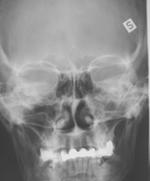

Perinteisenä NSO-rtg kuvauksena on ollut 1-3 kuvan sarja. Sarjaan on kuulunut suora etukuva (Caldwell-Luc), kuutamokuva (Waters) ja sivukuva. Lapsilta on tavallisesti tutkittu vain kuutamokuva. Perinteisen natiivikuvauksen ongelmana on huono osuvuus ja säderasitus. Säderasitus on liian iso jos kuvauksia on neljästi vuodessa. Tutkimuksen spesifisyys on korkea mutta sensitiivisyys matala.

Natiivikuvat: Suora etukuva (Caldwell-Luc), Kuutamokuva (Waters) ja sivukuva